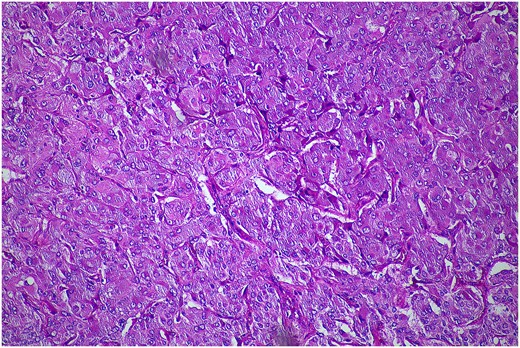

In February 2024, the patient underwent a left re-do retroperitoneoscopic completion adrenalectomy. Her postoperative course was uncomplicated, and she was discharged home within two days. The histopathology confirmed a low-risk phaeochromocytoma (Fig. 4). The plasma metanephrines normalized.

Histopathological examination of the excised lesion—from the second stage completion adrenalectomy—demonstrates characteristic features of a phaeochromocytoma. The section shows atypical polygonal cells with large hyperchrome nuclei, and cytoplasm with a granular appearance S100 (haematoxylin and eosin staining; 10× magnification). The cells are arranged in trabeculae and surrounded with s100 positive supporting cells.